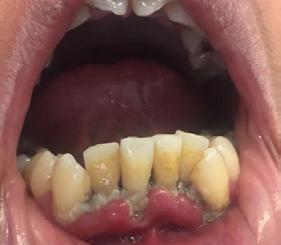

Caso 4

Se presenta un paciente de 43 años de edad con deficiente higiene dental y con gingivitis en el sextante anterior inferior del canino 33 al canino 43 presencia de bioplaca con puntuación de 3 mala y sarro subgingival, (Figura 11). Por la existente acumulación del sarro se recomendó realizar la profilaxis con el cavitron, el cual es un instrumento ultrasónico que trabaja con presión de agua y que facilita el detartraje (Figura 12).

Los programas de promoción y prevención se basan en la motivación que puede generarse en individuos y poblaciones acerca de realizar cambios en hábitos de

Dentista y Paciente 48 Caso clínico

higiene pretendiendo disminuir la concentración de microorganismos patógenos presentes en la boca. Una apropiada motivación, control y educación en higiene oral permitirá disminuir los riesgos de daño periodontal en pacientes sanos y conservar condiciones de salud expuestos a inflamación o enfermedad periodontal.6 A este paciente se le invitó a que realizara su limpieza dental con más frecuencia, y fue citado para revisión a los 15 días para ver el estado periodontal Figura 13. Observándose un cambio y mejoría de la encías, así como una menor cantidad de bioplaca, aunque no estaba todavía muy controlado su hábito de higiene, (Figura 13). Por lo que se citó para revisión en un mes.

Figura 11. Localización del sarro en la cara vestibular y lingual del canino 33 al 43.

Figura 12. A) Profilaxis con cavitron. B) Inserto del cavitron superficie labial OD 41. C) Eliminación del sarro por lingual y vestibular de canino a canino. Figura 13. Comparación vista inicio y control 13.